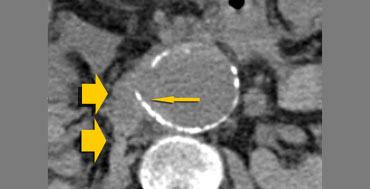

Dấu hiệu liềm tăng tỷ trọng ở bệnh nhân có bằng chứng rò rỉ nhẹ tiếp giáp cơ thắt lưng phải (mũi tên rộng).

Liềm tăng tỷ trọng

Hình ảnh liềm tăng tỷ trọng đại diện cho khối tụ máu cấp tính nằm trong huyết khối thành mạch hoặc thành túi phình.

Dấu hiệu này có liên quan chặt chẽ với vỡ phình động mạch chủ bụng.

Độ nhạy của dấu hiệu liềm tăng tỷ trọng như một chỉ điểm của phình động mạch chủ có biến chứng là 77%; độ đặc hiệu 93%; và giá trị tiên đoán dương tính 53%.

Do đó, ngay cả khi không có dấu hiệu vỡ chính, chúng ta vẫn cần thông báo cho bác sĩ lâm sàng rằng bệnh nhân này có nguy cơ rất cao bị vỡ phình động mạch chủ trong vài ngày tới.

Bên trái là hai trường hợp khác của dấu hiệu liềm tăng tỷ trọng.

Trong trường hợp bên phải, chúng ta cũng có thể xác định được khối tụ máu sau phúc mạc, do đó trong trường hợp này đã có vỡ phình động mạch chủ bụng hoàn toàn.